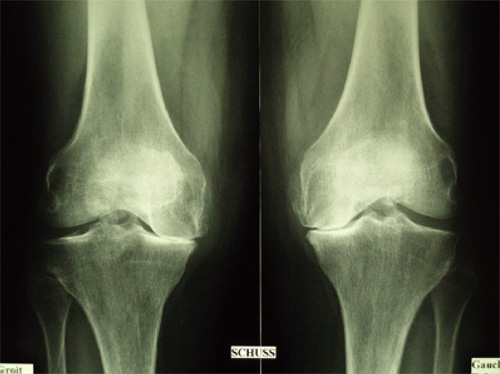

L’ostéotomie tibiale de valgisation est un des traitements chirurgicaux de la gonarthrose, surtout de la gonarthrose médiale (interne). Elle est réalisée pour traiter l’arthrose d’un seul compartiment du genou lorsque la prothèse totale du genou n’est pas indiquée et lorsqu’on peut se passer de prothèse uni-compartimentale.

L’ostéotomie tibiale de valgisation a pour but de rééquilibrer l’axe du membre inférieur et donc les pressions au niveau de l’articulation fémoro-tibiale du genou.

Le but de l’ostéotomie tibiale de valgisation est de transformer un génu-varum (jambe arquée) en génu-valgum afin de diminuer les contraintes du côté usé et de les reporter sur le côté sain, c’est-à-dire sur le côté externe en cas d’arthrose fémoro-tibiale interne. On ne remplace donc pas le côté usé mais on diminue très fortement les douleurs grâce à la diminution des sollicitations en pression et en retardant l’usure on retarde également la mise en place d’une prothèse du genou.